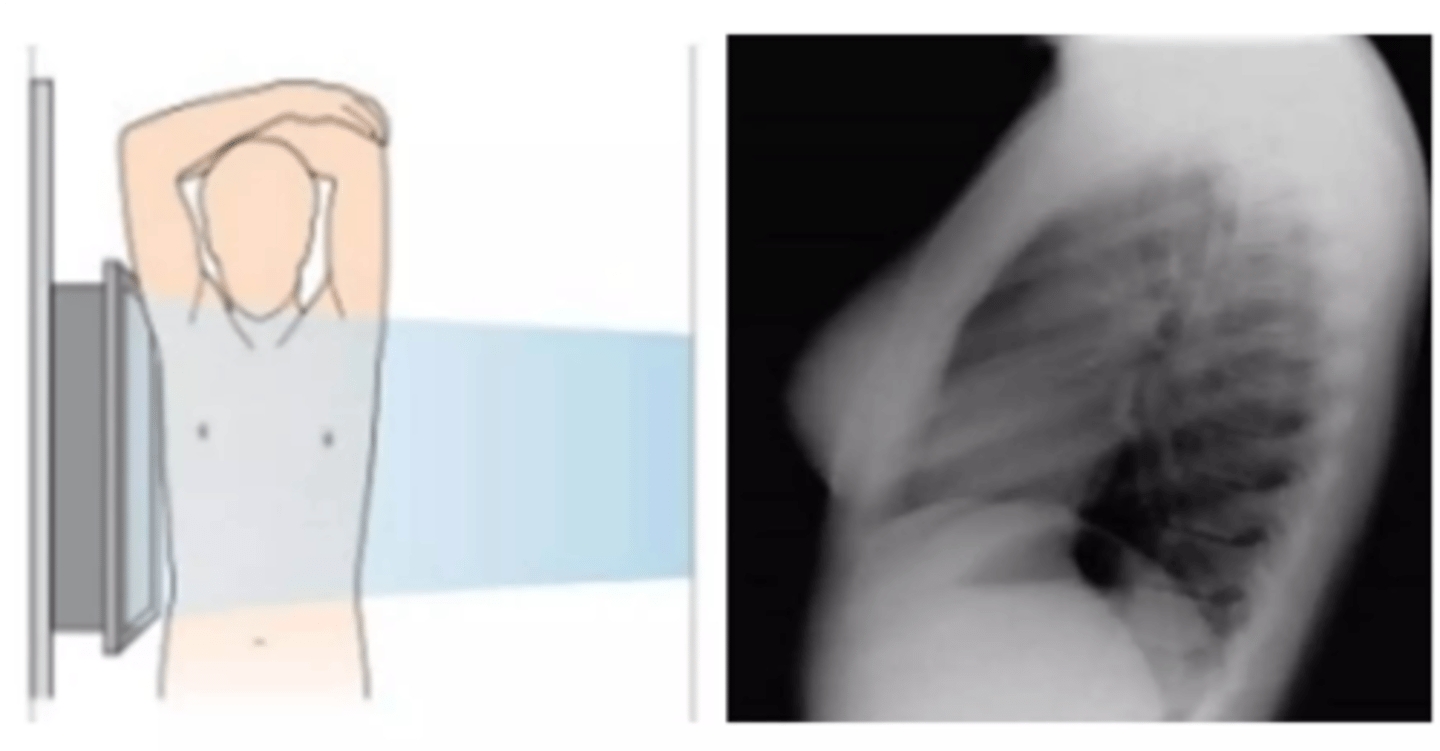

Lateral view